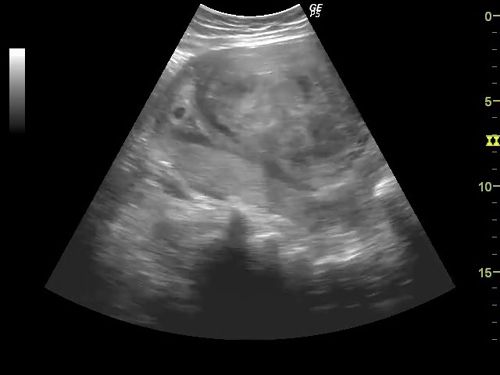

This image quiz focuses on the kidneys. Can you identify the abnormality seen in these ultrasound images of the fetal abdomen?